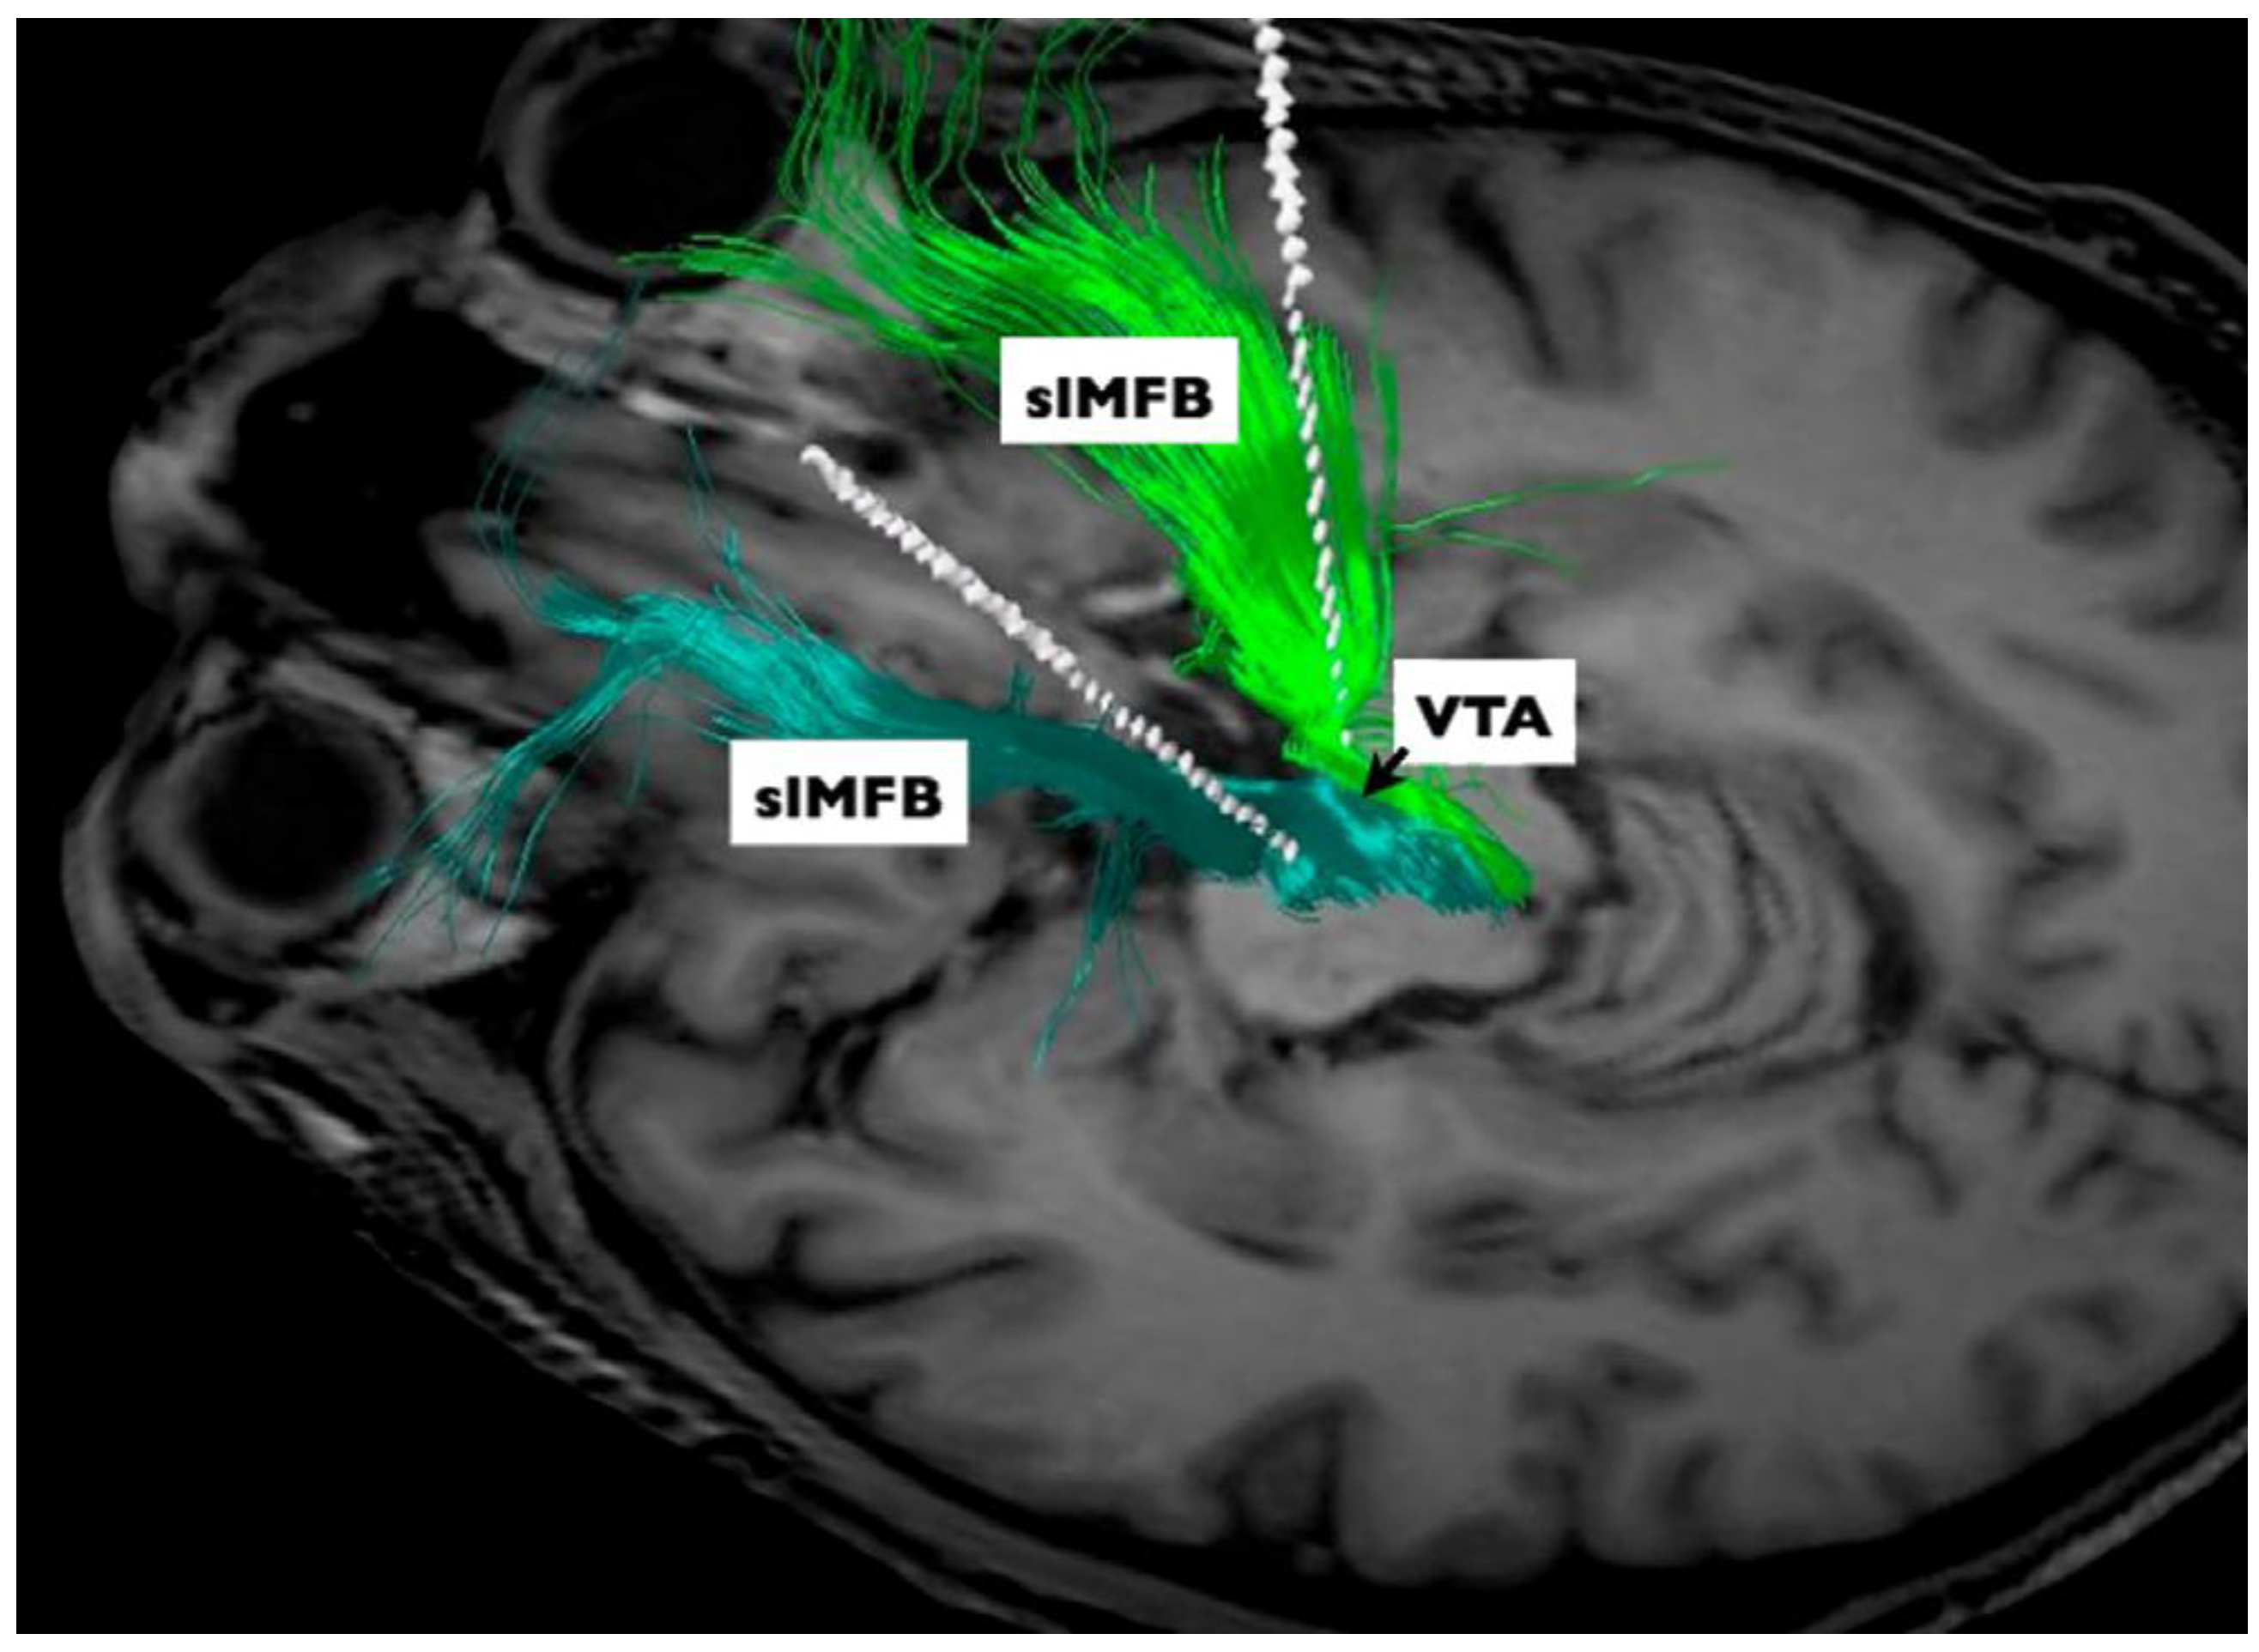

- Coenen, V.A.; Panksepp, J.; Hurwitz, T.A.; Urbach, H.; Madler, B. Human medial forebrain bundle (MFB) and anterior thalamic radiation (ATR): Imaging of two major subcortical pathways and the dynamic balance of opposite affects in understanding depression. J. Neuropsychiatry Clin. Neurosci. 2012, 24, 223–236. [Google Scholar] [CrossRef] [PubMed]

- Coenen, V.A.; Schlaepfer, T.E.; Maedler, B.; Panksepp, J. Cross-species affective functions of the medial forebrain bundle-implications for the treatment of affective pain and depression in humans. Neurosci. Biobehav. Rev. 2011, 35, 1971–1981. [Google Scholar] [CrossRef] [PubMed]

- Bewernick, B.H.; Kayser, S.; Gippert, S.M.; Switala, C.; Coenen, V.A.; Schlaepfer, T.E. Deep brain stimulation to the medial forebrain bundle for depression-long-term outcomes and a novel data analysis strategy. Brain Stimul. 2017, 10, 664–671. [Google Scholar] [CrossRef] [PubMed]

- Schlaepfer, T.E.; Bewernick, B.H.; Kayser, S.; Madler, B.; Coenen, V.A. Rapid effects of deep brain stimulation for treatment-resistant major depression. Biol. Psychiatry 2013, 73, 1204–1212. [Google Scholar] [CrossRef] [PubMed]